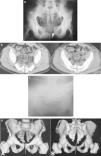

Se posicionó al paciente en decúbito prono en la mesa de operaciones con todo lo necesario para dar cabida al fijador externo colocado en la parte anterior de la pelvis. Se practicó, a ambos lados de la pelvis, una incisión vertical 1cm lateral a la espina ilíaca posterosuperior, que se extendió hacia la distal. La superficie del ilíaco lateral a la espina ilíaca posterosuperior se abordó subperiósticamente separando hacia un lado el glúteo mayor. Se marcó en la piel el espacio interespinoso S1-S2. A esta altura se realizó un orificio a ambos lados y se introdujo un trocar por vía artroscópica para preparar el túnel en el que posteriormente se colocaría una barra transilíaca. Se introdujo una barra roscada tipo Ilizarov (fig. 2a). Se utilizó una tuerca y una arandela a ambos lados para estabilizar el anillo en la zona posterior. No se intentó cerrar la fractura sacra ya que se pensó que esto podría resultar peligroso sin control directo del lecho fractuario para evitar un atrapamiento neural.

Tras la intervención, el paciente registró una disminución del dolor y consiguió una sedestación cómoda. También era capaz de realizar elevaciones de pierna recta bilaterales sin dolores ni molestias. Su estado neurológico se mantuvo sin cambios. Debido al poco habitual patrón fractuario presente en el sacro, se estudió minuciosamente la historia clínica anterior del paciente y se descubrió que se le había practicado una TAC de columna lumbar 5 años antes, sin que se hubiera detectado ninguna anomalía evidente (fig. 2b).